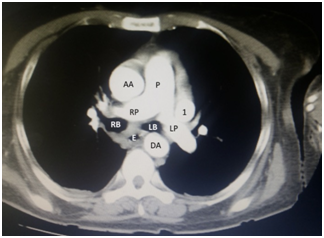

Figure 2 Caudal section from Figure 1. LSVC running through the left side of the mediastinum towards the heart.

AA: Ascending Aorta; DA: Descending Aorta; P: Pulmonary Trunk; RP: Right Pulmonary Artery; LP: Left Pulmonary Artery; RB: Right Principal Bronchus; LB: Left Principal Bronchus; E: Esophagus